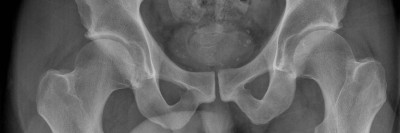

Bildnachweise

Laparoskopische Operation/© Iryna / stock.adobe.com (Symbolbild mit Fotomodellen), Pincer-Konstellation, Hüftdysplasie und CAM-Impingement im Röntgenbild/© Fehske K / all rights reserved Springer Medizin Verlag GmbH, Ultraschallbefund einer klassischen sekundären Hydrozele/© Filmar, S., Gross, A.J., Hook, S. et al. , Nuck-Zyste/© Oehring R & Farke S / all rights reserved Springer Medizin Verlag GmbH, Arzt macht Ultraschall bei älterem Mann/© bojanstory / Getty Images / iStock (Symbolbild mit Fotomodell), Operation einer Leistenhernie links nach Lichtenstein/© Dietz U A et al. / all rights reserved Springer Medizin Verlag GmbH, Leistennaht nach Hernien-Operation/© Michael Weber / imageBROKER / mauritius images, De-Garengeot-Hernie/© Abazid A et al. / all rights reserved Springer Medizin Verlag GmbH, Liposarkom des Funiculus spermaticus/© Springer Medizin Verlag GmbH, Search Icon, Knochensäge im Einsatz bei Knie-TEP/© Issara / stock.adobe.com (Symbolbild mit Fotomodellen), Hirntumoren sichtbar im MRT/© semnic / Getty Images / iStock (Symbolbild mit Fotomodell), Lungentrainer/© S@photo / stock.adobe.com (Symbolbild mit Fotomodell)